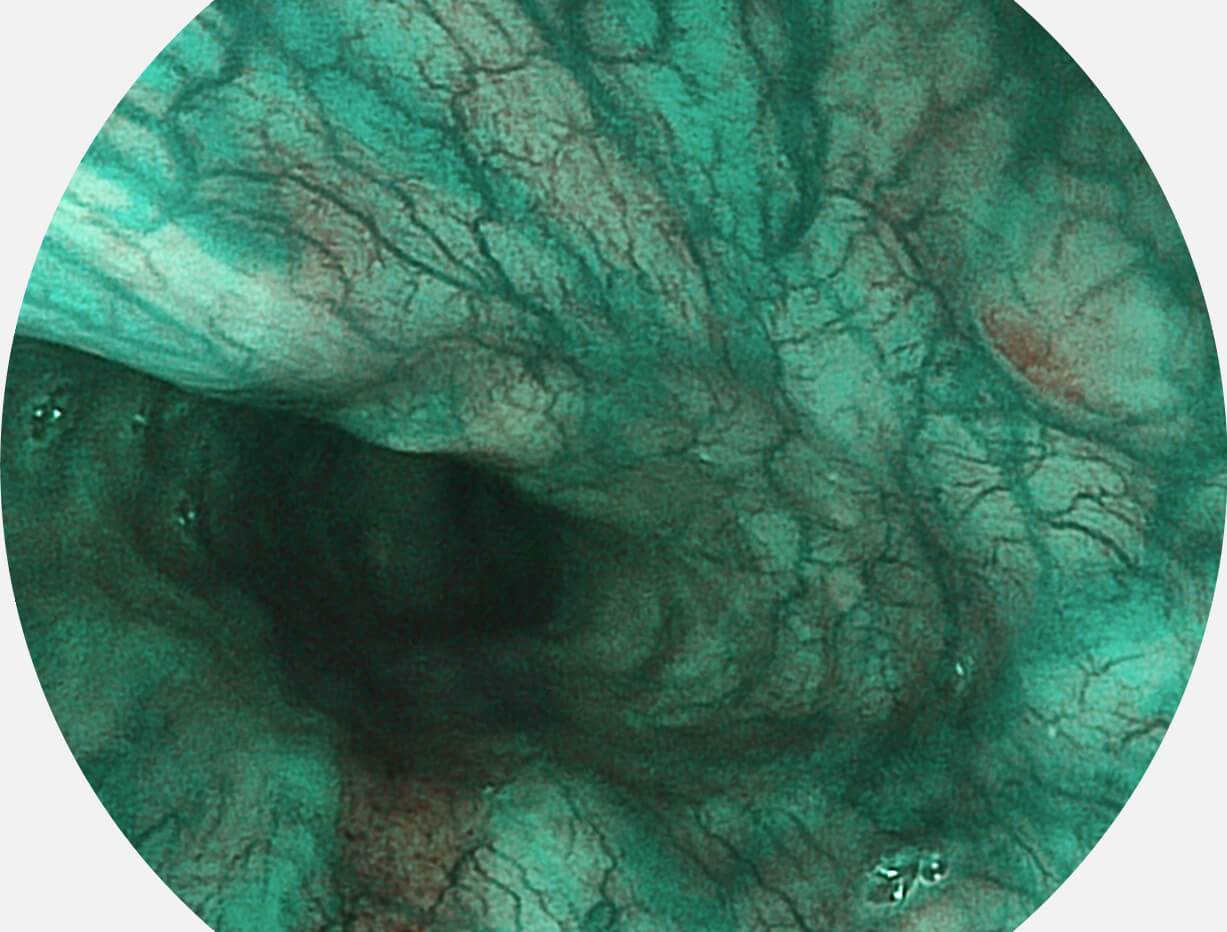

Spectral Focused lmaging, SFI

图像具有高亮度、高黏膜血管颜色对比度的特点,且不改变粘液、食物残渣、粪便的基本颜色,可在中远景下进行观察,助力消化道早期疾病的诊断。

白光图像

SFI图像